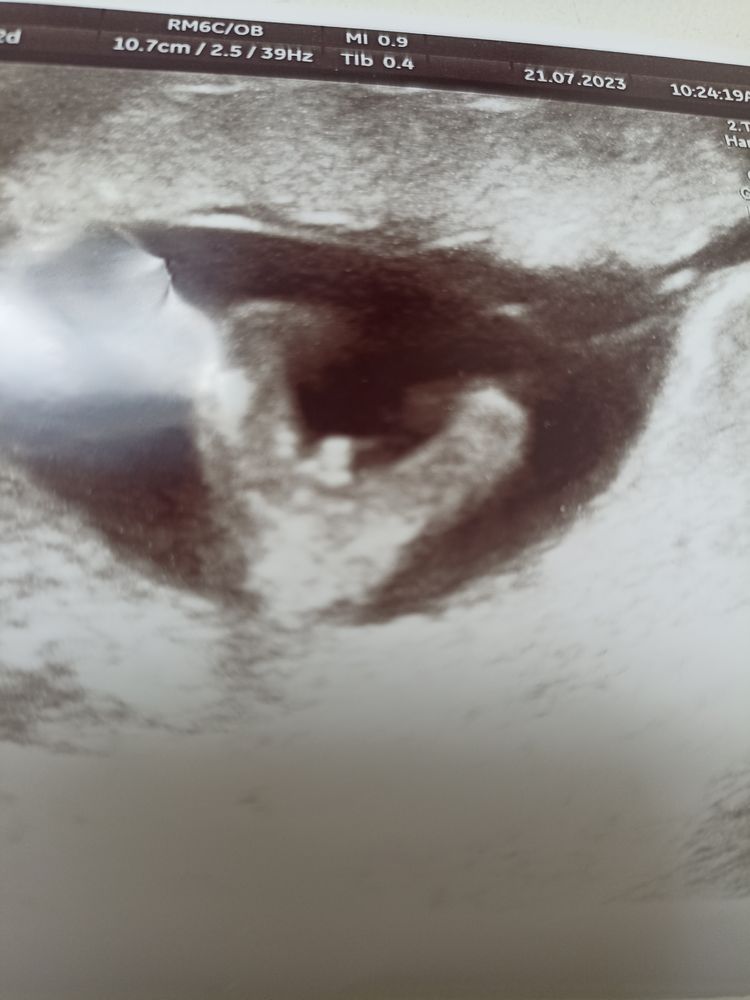

У меня такая ситуация сложилась...на 12 неделе сделали плановое УЗИ- где врач чётко сказала, что пол ребенка - мужской💙.... И фото ещё такое прям скажешь точно - мальчик😊 Но ведь есть женское предчувствие, плюс к этому - женщина, которая высчитала мне девочку, ещё никому не путала на протяжении 18 лет....После 2-ух мальчиков, так хочется верить что девочка....

У вас на блоге читала, что бывало на таком сроке путали пол ребенка с пуповиной.... вот и мои сомнения обострились отсюда.... поэтому и обращаюсь к вам...

Прилагаю фото УЗИ🖼️

В 12 недель у плода половой бугорок и то фото что Вы приложили актуально и для девочек и для мальчиков, а вот после 15 недель уже будет видна половая принадлежность. В 12 недель правильно пол может определить только хороший узист, если у Вас такая и была, то есть большая вероятность что она права, но точно узнаете чуть позже. По поводу женщины что высчитывает пол, у нас на юге это распространено, моим сестра тоже высчитывали, у них получилось, а у многих других нет, так что это вилами по воде писано))

В 11 недель была на узи, сказали что мальчик , я еще удивилась откуда там может быть видно пол , очень рано же , она говорит очень видно органы 😃 ну видно так видно, за день до скрининга в 12 недель ровно получаю результат по крови - девочка ) иду на скрининг , там мне показывают что пуповина лежит ровно между ножек) поэтому наверно и перепутали в 11 недель) вообщем там все очень неточно) сдайте кровь и будем вам точный ответ через неделю)